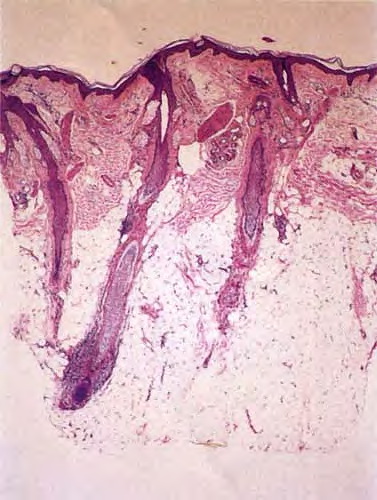

As telogen follicles reenter anagen, they again come under attack from pathogenic lymphocytes, which precipitate premature conversion to catagen once again, so that anagen duration becomes shorter and shorter and the follicles begin to miniaturize . As the follicles decrease in size they become situated more superficially, although often deeper than normal vellus hairs, with their bulbs situated in the mid to lower dermis . With disease chronicity, most of the hairs become miniaturized. Miniaturization and conversion to catagen and telogen leave many collapsed fibrous root sheaths in the subcutis.

Whiting found that transversely sectioned scalp biopsies showed the diagnostic features of alopecia areata more often than vertically sectioned biopsies . He also published mean quantitative hair counts for horizontally sectioned scalp biopsies of alopecia areata. The mean terminal-ta-vellus hair ratio was similar to that seen in androgenetic alopecia , reflecting extensive miniaturization. The mean anagen-ta-telogen ratio was 73%:27%, and the total hair count (mean of 27 hairs) was 33% less than in the control group, with more severely affected patients (alopecia universalis) at the lower end of the spectrum. Others have also found that the follicular density can decrease in severe alopecia totalis and universalis of long duration (a decade or more), with scars replacing some of the follicular sheaths .